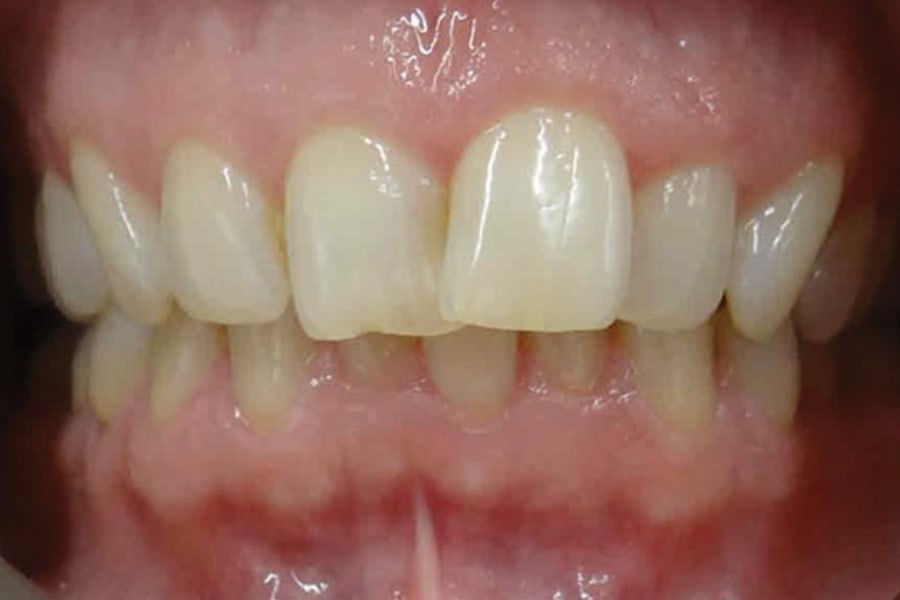

A 54-year-old woman presented with a chief complaint of teeth crowding. After comprehensive digital records were obtained, ClearCorrect® aligner therapy (Straumann, clearcorrect.com) was chosen with an anticipated 12-month treatment duration. The patient exhibited moderate anterior crowding, a class II molar relationship, and narrow arches. The treatment plan aimed to resolve the class II discrepancy, expand the arches, and establish proper anterior alignment. A total of 25 active aligners plus two retention aligners were prescribed. Attachments were selectively placed on the maxillary and mandibular canines to premolars, minimizing bulk while maintaining control over torque and posterior alignment. The patient was instructed to wear class II elastics full-time, which was crucial to achieving molar correction and arch expansion. Her outstanding compliance with class II elastics contributed to a significant improvement in molar position and transverse arch development. After completing the active phase, the patient transitioned to retainers to ensure long-term stability of the results. Given the patient’s initial class II occlusion, monitoring retention was emphasized to prevent relapse. The patient was extremely pleased with the outcome, demonstrating a broadened smile and improved occlusal function. This case underscores the effectiveness of ClearCorrect’s aligners in adult patients, particularly when combined with compliant elastic wear and targeted expansion strategies.